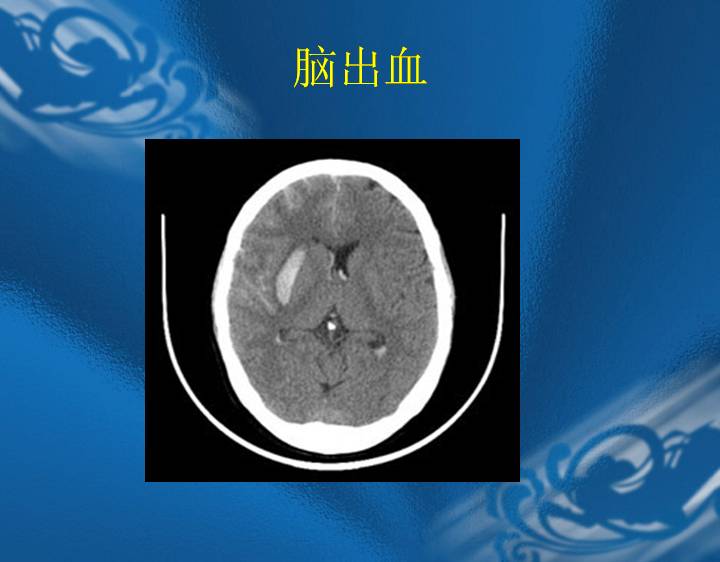

执业医师资格考试“实践技能”影像学辅导资料